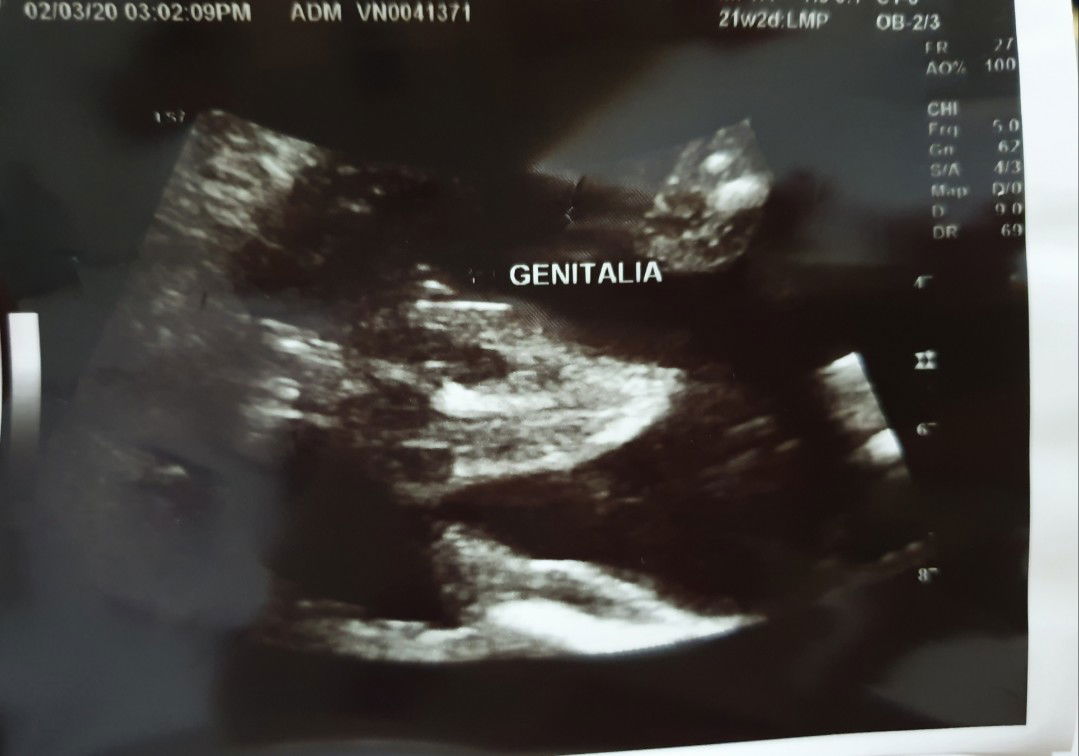

Gender? girl or boy?

Mga momsh! Please enlighten me..is it a boy or girl? Sabi ng ob sono girl naman daw kaya napapabili nako ng pang girl kaso baka mamaya lalaki pala haha. Thank you